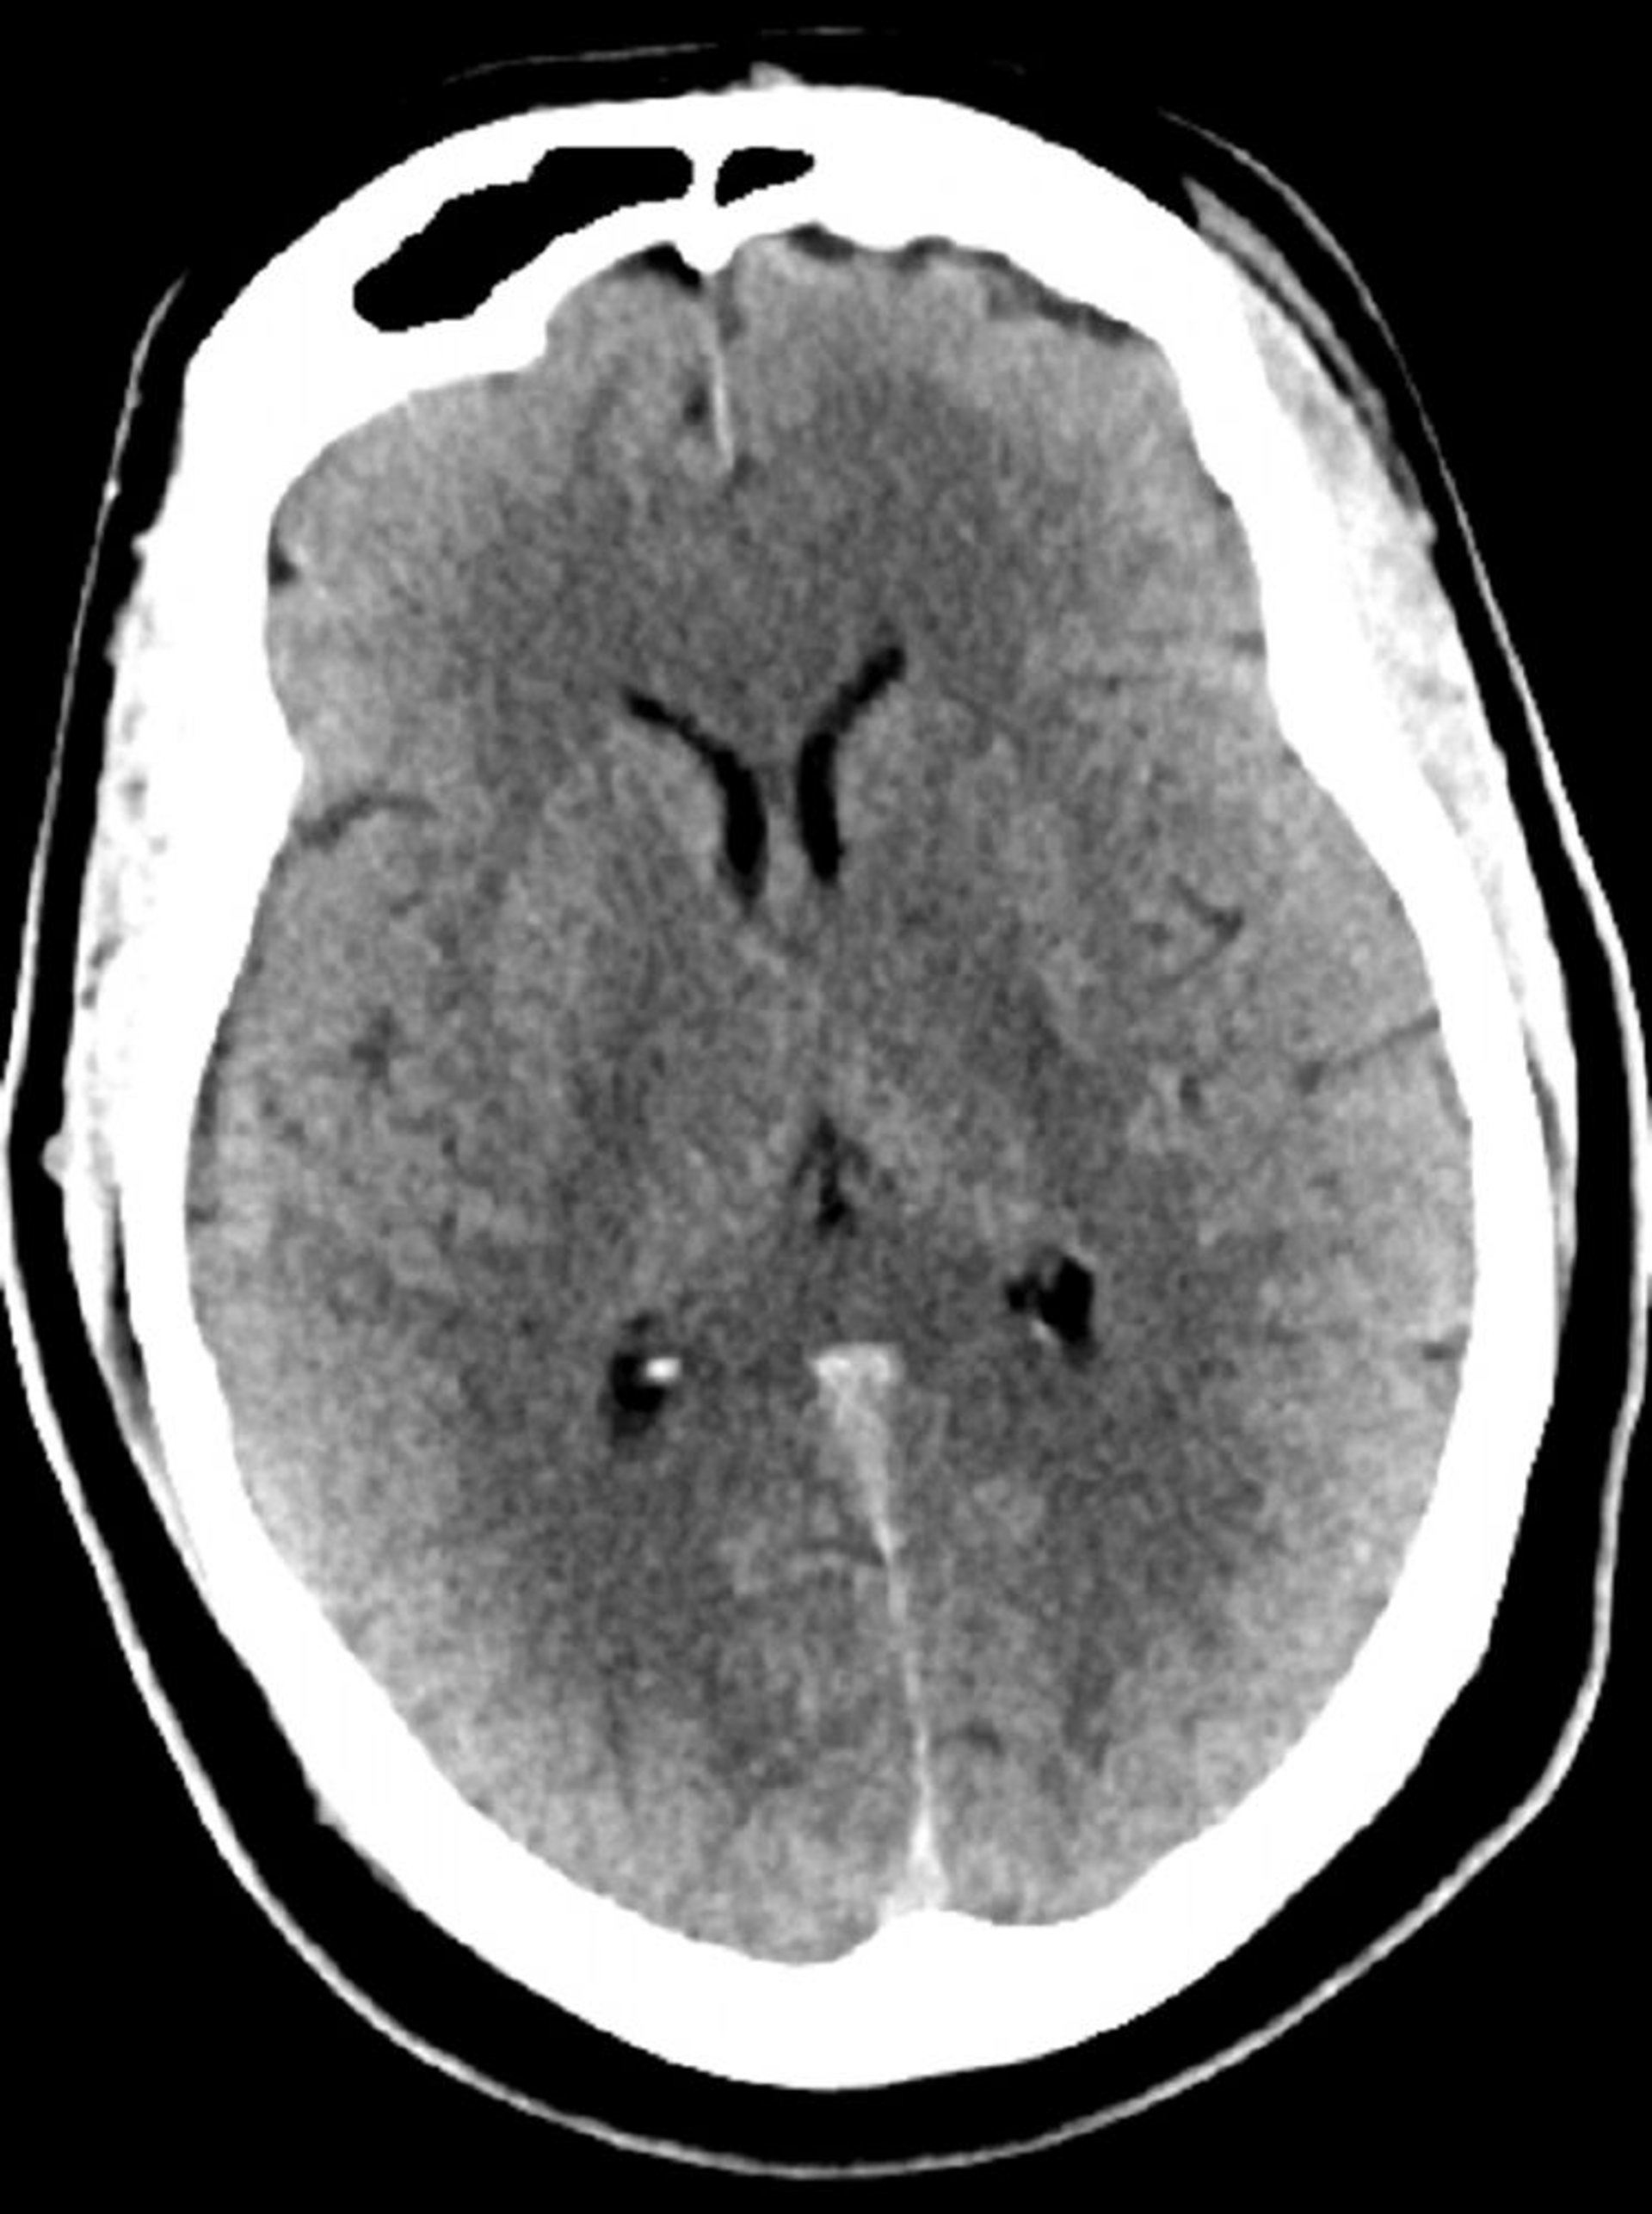

Tomografía computarizada craneal normal (adulto, 30 años)–diapositiva 5

Esta imagen es una tomografía computarizada craneal normal correspondiente a un adulto joven de 30 años de edad. No hay hemorragia o líquido intra- o extra axial. Se conserva la diferenciación gris-blanco. El tamaño ventricular y el patrón sulcal son normales.